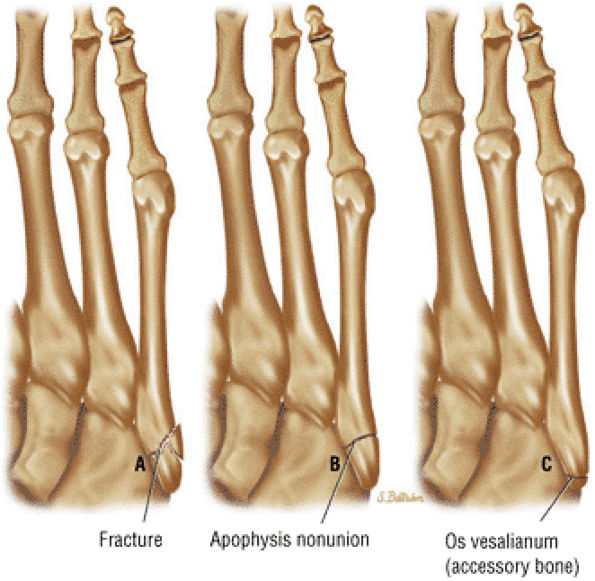

FIGURE 5.92 ● Anterolateral and posteromedial locations of osteochondral lesions of the talus. The lateral lesions tend to be shallower and wafer-shaped, whereas the medial lesions are deeper and cup-shaped.